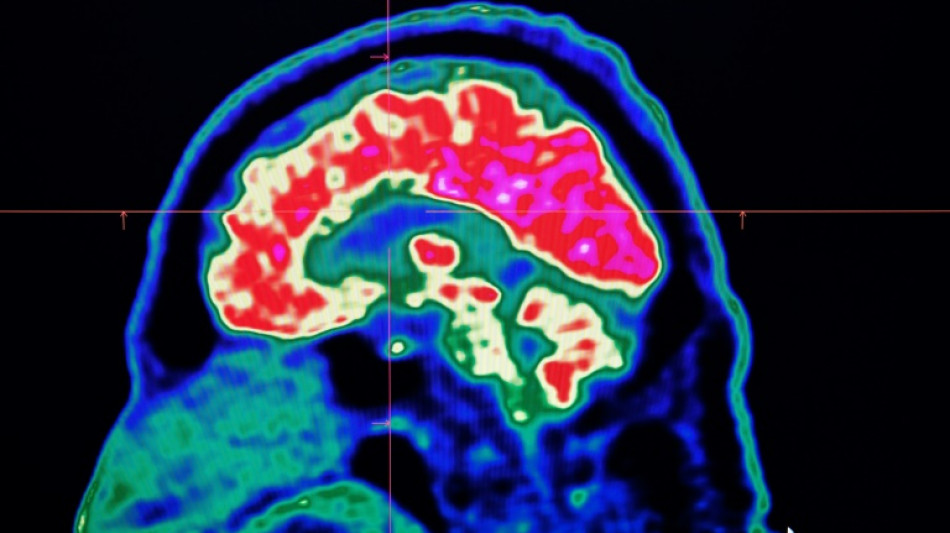

Conditions affecting the nervous system -- such as strokes, migraines and dementia -- have surged past heart disease to become the leading cause of ill health worldwide, a major new analysis said on Friday.

More than 3.4 billion people -- 43 percent of the global population -- experienced a neurological condition in 2021, far more than had previously been thought, the analysis found.

Lead study author Jaimie Steinmetz of the IHME said the results showed that nervous system conditions are now "the world's leading cause of overall disease burden".